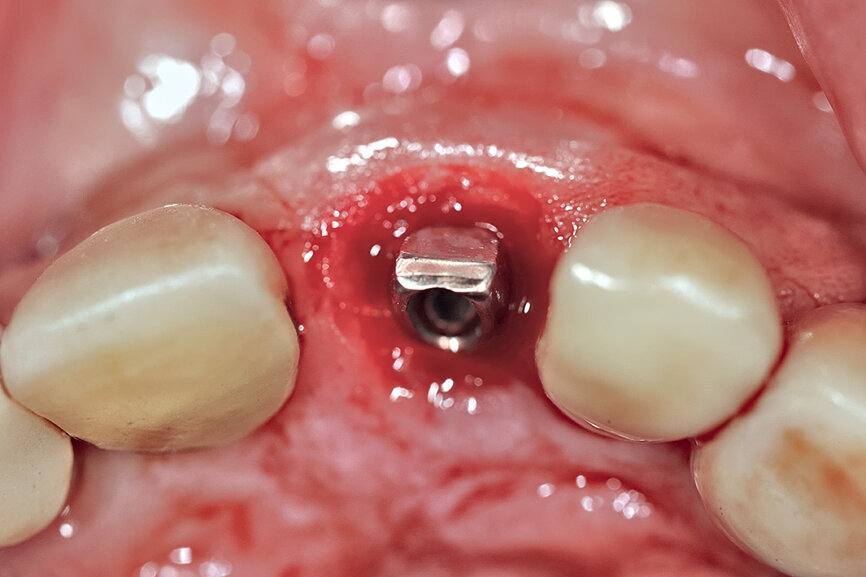

Fig. 1: The patient presented with a horizontally fractured clinical crown, an indication for a partial extraction therapy procedure.

One indication for PET is when a patient presents with a horizontally fractured clinical crown (Fig. 1). While a 2D radiograph will reveal the extent of the horizontal fracture, length of the remaining root and approximation of the bone apical to the root, there is not enough information to plan for a PET procedure. A CBCT scan is recommended in order to fully appreciate the root position within the alveolus and the potential difference between the trajectory of the bone and the trajectory of the root as can be visualised with a cross-sectional image (Fig. 2). Utilising interactive treatment planning software makes it possible to plan the initial drill path to accurately section the root to its apex (Fig. 3a). This can be accomplished by creating a custom implant design to match the diameter of the initial drill with an abutment projection in order to fully appreciate the trajectory through the clinical crown (Blue Sky Plan, Blue Sky Bio). It is important to visualise the root fragment that will remain in order to properly simulate the position of the implant in the alveolus (Fig. 3b). The apical portion of the implant can be positioned to gain stability in host bone using the Triangle of Bone. It is important to note that a cross-sectional slice may only be 0.125 mm in thickness based on the CBCT acquisition, and therefore all images in all views must be visualised to confirm the plan. Utilising 3D segmentation (separating objects by density values), it is possible to define each root and further assess the simulated position of the implant with a sagittal cut through the 3D reconstructed volume (Fig. 4).